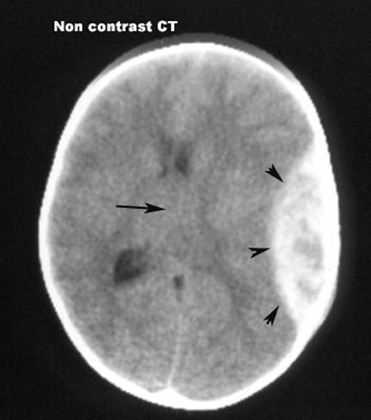

Dandy Walker Syndrome merupakan suatu sindrom (kumpulan gejala) yang terjadi pada seorang anak akibat tidak terbentuknya “pintu keluar” cairan otak dari dalam kepala. Dalam bahasa medis, pintu keluar ini disebut dengan suatu lubang khusus yaitu yang dinamakan dengan “Foramen Luschka dan Magendie”. Dalam teorinya, cairan otak manusia tersebut berada di dalam rongga cairan otak yang setiap hari diproduksi di dalam kepala dan setiap hari juga dibuang ke tubuh kita. Pada kondisi tertentu terjadi gangguan aliran cairan otak tersebut sehingga terjadilah penumpukan cairan otak yang disebut dengan “Hidrosefalus”. Hal ini akan berdampak terjadinya pembesaran rongga cairan otak yang akan menekan jaringan otak di sekitarnya. Pada Dandy Walker Syndrome, tidak terbentuknya pintu keluar ini yang mengakibatkan gangguan aliran cairan otak, pembesaran pada rongga cairan otak di sekitar otak kecil (ventrikel IV), disertai pula dengan terbentuknya kista besar di daerah otak kecil (serebelum), sehingga sebagian otak kecil (bagian tengah dari otak kecil) kemudian tidak tumbuh. Tidak tumbuhnya ini kemungkinan karena terhambat oleh kista berisi cairan otak yang menumpuk tersebut.

Penderita Dandy Walker Syndrome dapat disertai dengan hidrosefalus atau juga tidak. Dari beberapa rujukan menunjukkan angka sekitar 70-80% penderita Dandy Walker Syndrome juga disertai dengan hidrosefalus. Hidrosefalus ini disebabkan oleh gangguan aliran cairan otak seperti yang saya jelaskan diatas.

Tindakan bedah saraf yang dilakukan untuk penderita Dandy Walker Syndrome adalah dengan pemasangan selang pintasan dari daerah otak kecil (tempat kista berada) ke perut, disebut juga dengan “Cystoperitoneal shunt”. Bila terdapat hidrosefalus, maka dipasang juga selang pintasan dari rongga cairan otak menuju rongga perut (Ventriculoperitoneal shunt; VP SHUNT). Pemeriksaan oleh bidang spesialistik lain sangat diperlukan untuk mencari kemungkinan gangguan pada sistem organ yang lain, dan terapi harus dilakukan bila memang terindikasi.